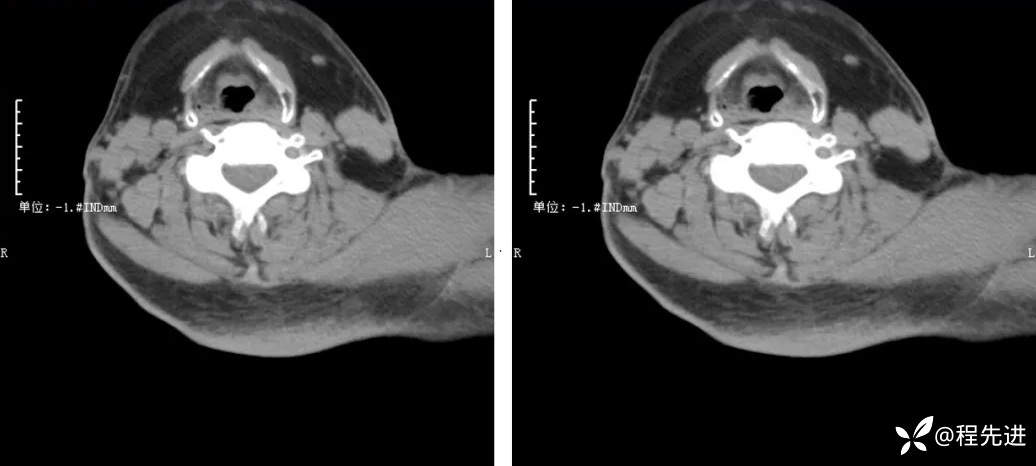

CT检查: